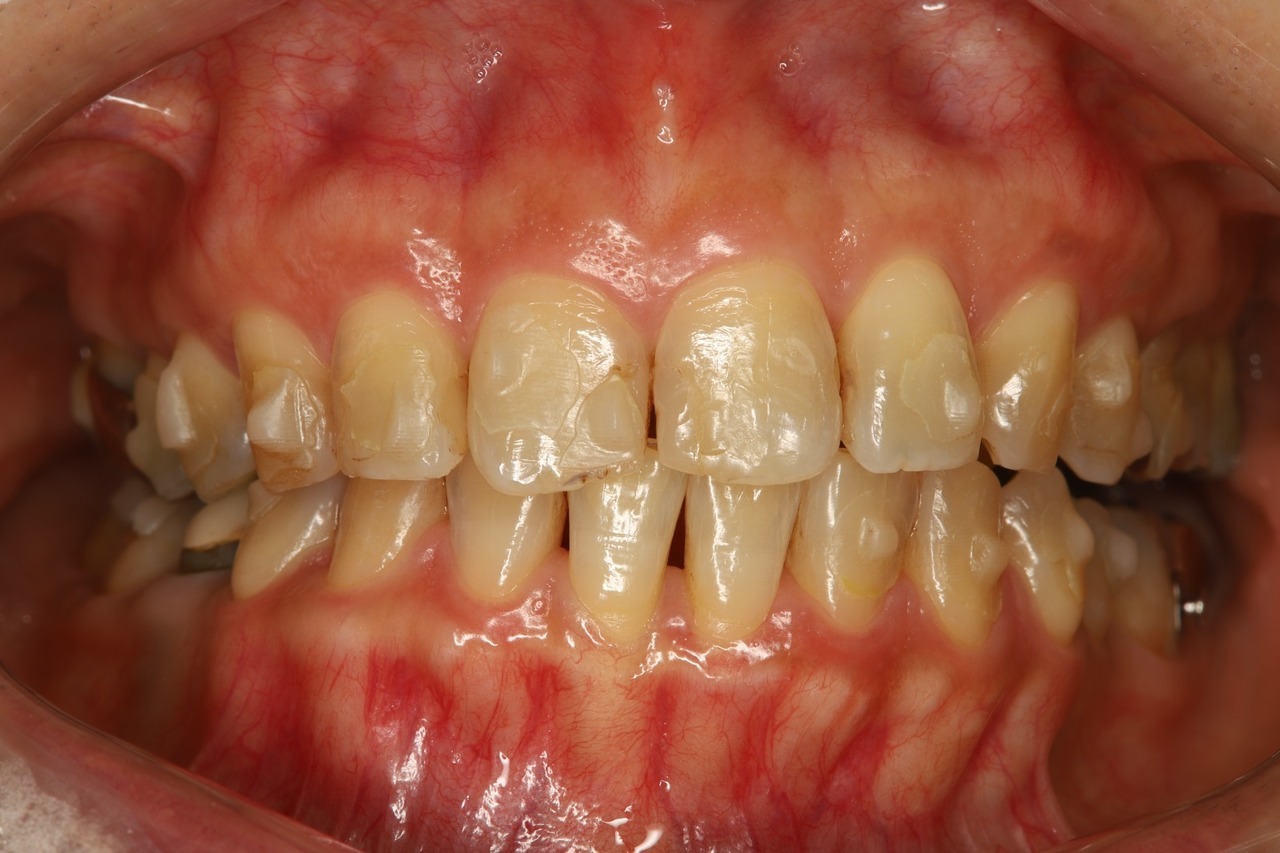

当院でのインビザライン治療例

こちらは当院でマウスピース矯正を行った患者さまです。前歯だけでなく奥歯の咬み合わせまで含めて調整することで、将来的な歯の健康や歯並びの安定を守ります。

出っ歯が治り、歯と歯の間に隙間もありません。

奥歯がしっかりと噛み合い、安定した咬み合わせになっています。